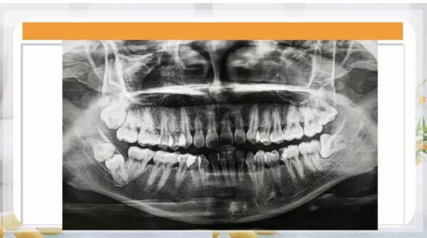

最近朋友圈轉(zhuǎn)發(fā)最多的一張片子,你知道嗎?

1.png